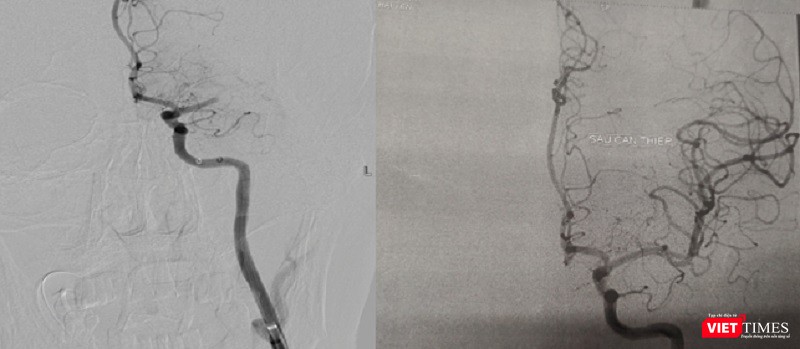

Ngay lập tức, hai cuộc phẫu thuật được thực hiện cùng lúc để cấp cứu bệnh nhân. Hai ekíp bác sĩ can thiệp thần kinh và can thiệp mạch vành nhanh chóng thống nhất phương án xử lý và quyết định thứ tự các kíp can thiệp, bắt đầu hút huyết khối để tái thông dòng chảy trên hệ mạch máu não trước, sau đó tiến hành can thiệp đặt stent động mạch vành cho bệnh nhân.

Hình ảnh động mạch não trước và sau khi hút huyết khối